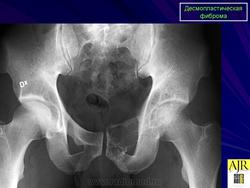

Десмопластическая фиброма редкая локально агрессивная внутрикостная опухоль, характеризующаяся продукцией опухолевыми клетками пучков коллагеновых волокон. Встречается в любом возрасте (чаще у лиц моложе 30 лет), с равной частотой у мужчин и женщин. Локализуется в основном в эпифизах и метафизах длинных костей (бедренная, плечевая, большеберцовые кости), плоских костях (кости таза, лопатка), нижней и верхней челюстях.

Рентгенологически остеолитический очаг, вызывающий вздутие истончённой кортикальной пластинки.

Десмопластическая фиброма